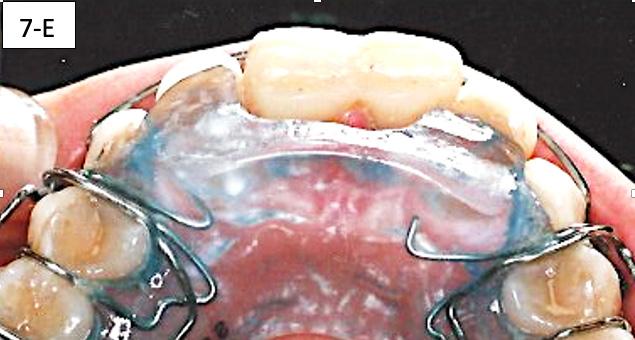

After the mandibular second molars became firmly in contact with the maxillary molars, a Maxillary removable protrusive appliance (Twin block II) with hooks was inserted to maintain the therapeutic position with the recaptured disks. Also, composite build-up was bonded to the lingual surface of #11(8) and #21(9), to maintain the mandible in the same position. Three ¼” – 4.5 oz triangular elastics were placed for forced eruption of the mandibular first molars and bicuspids. Separators were placed between the mandibular molars and bicuspids to speed up the elevation of the posterior sextants (figure 7-E, F, G).

FIG. 7E: Protrusive appliance and composite build-ups

FIG. 7F: Forced eruption of mandibular posterior sextants

FIG. 7G: Forced eruption of mandibular posterior sextants